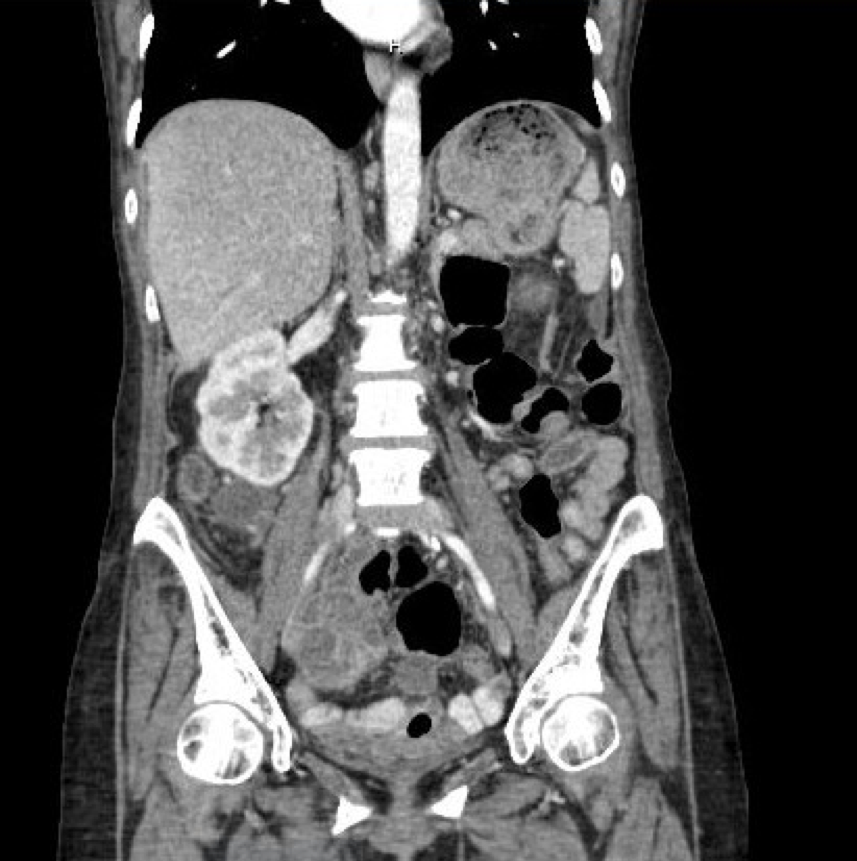

We present an unusual presentation of a chronic appendicular abscess. A 57-year-old presented to the emergency department with acute on chronic abdominal pain, worsening discomfort, abdominal distention and decreased appetite. Abdominal imaging revealed the presence of multiseptated cystic right adnexal mass, concerning for metastatic ovarian carcinoma. Intra-operatively the diagnosis of a likely chronic ruptured appendix at the base of the colon was confirmed.References